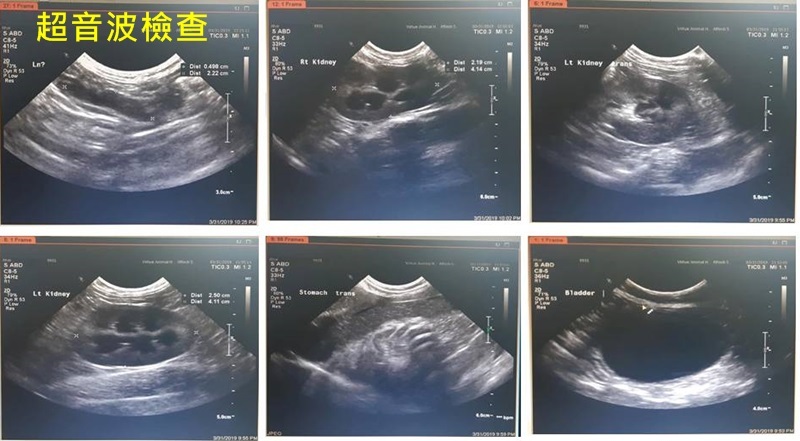

醫師為阿海量體溫、進行血檢、X光及超音波檢查,結果阿海發燒、血況再往下掉,血容比從27掉到22、白血球指數只剩1200,貓小病毒快篩陰性、X光無胸水,醫師幫阿海上靜脈注射、打抗生素、吸氧,希望能盡快穩住病情。